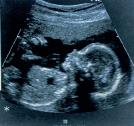

Tato technika se používá mimo jiné k zobrazování dítěte v těle matky. Do těla jsou vysílány neslyšitelné, velmi krátké zvukové vlny, které se odrážejí od vnitřních orgánů a vytvářejí odezvy, které počítač mění v obrázky.

Tento ultrazvukový snímek ukazuje trojčata rostoucí v téže děloze. Každý plod je obklopen vlastním plodovým vakem.